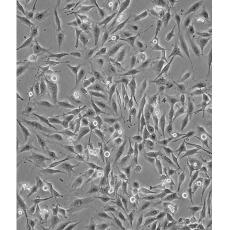

產品名稱 MDA-MB-435S

中文名稱 人乳腺導管癌細胞

組織來源 previously described as: mammary gland/breast; derived from metastatic site: pleural effusion

細胞種屬 Homo sapiens, human

生長特性 adherent

培養基 DMEM+0.01mg/ml bovine Insulin+0.01mg/ml Glutathione+10% FBS+1% P/S

形態特征 spindle shaped

傳代方法 1:3-1:6

培養條件 Atmosphere: Air, 95%; CO2, 5%。Temperature: 37℃

細胞描述 MDA-MB-435S是一種紡錘形的細胞,1976年由其親本(435)中篩選得到。435是從31歲的轉移性乳腺導管腺癌女性患者胸水中分離得到。當用熒光染料對微管蛋白進行染色時親本細胞顯現散布特征(II型)。最近通過cDNA陣列研究表明,親本(MDA-MB-435)可歸入黑素瘤起源。